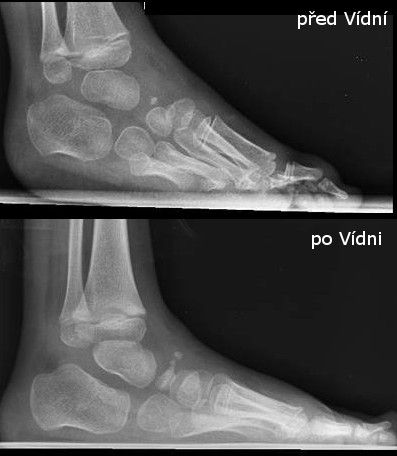

Ve Vídni působí nejbližší certifikovaný lékař Ponseti metody Dr. Christofer Radler, a to byla jejich poslední naděje. I když to znamenalo každý týden 8 hodinovou cestu a úhradu všech lékařských úkonů (neboť zde neplatí naše pojištění).

Bylo potřeba začít úplně od začátku – znovu 5 sáder (konečně správně dle Ponseti metody)  a opět udělat malý operační zákrok (tenotomie).

A tady je konec dlouhé cesty Písek – Praha – Brno – Vídeň, mnoha naježděných kilometrů a velké odvahy jít si za svým.

Dnes má malá Natálka 6 let, nejhorší období má za sebou a se správnou léčbou to zvládla i bez operací. Má velkou naději na plnohodnotný život bez omezení a bolestí.